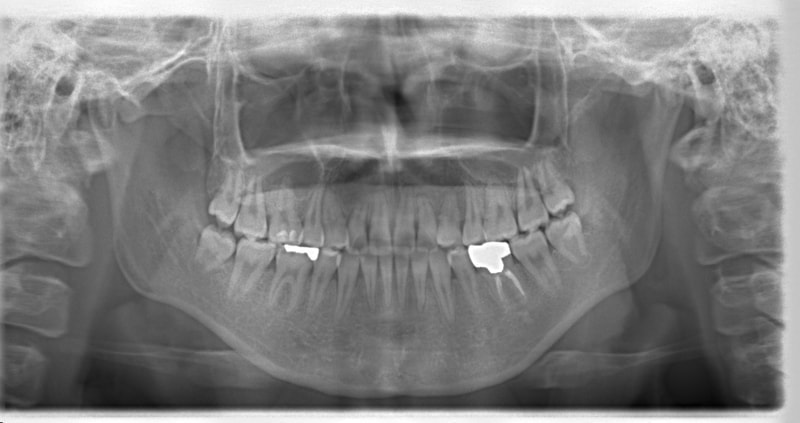

治療開始時